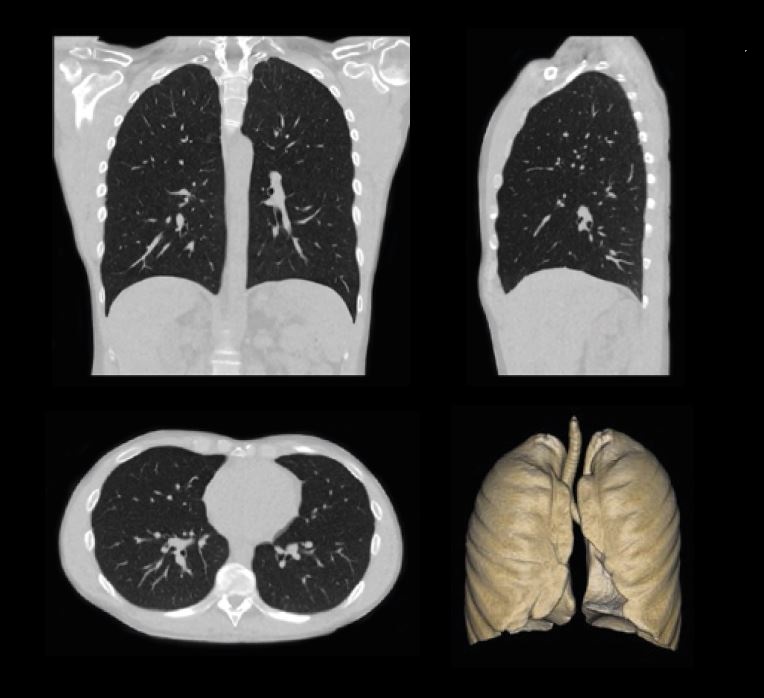

КТ легень, отримана за допомогою техніки SilverBeam, CTDIvol 0,6 / DLP 24,5.